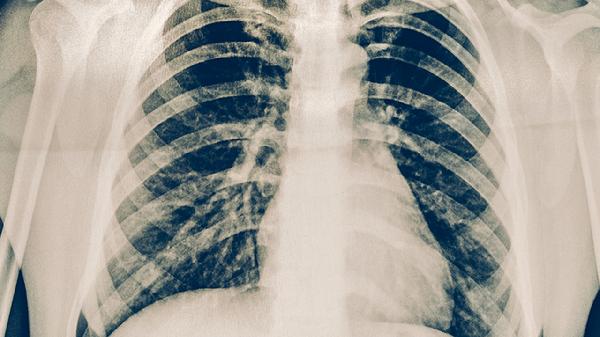

肺癌位于氣管旁多數(shù)情況下可以手術(shù)切除,具體需評估腫瘤大小、侵犯范圍及患者心肺功能。手術(shù)可行性主要取決于腫瘤與氣管的解剖關(guān)系、是否存在淋巴結(jié)轉(zhuǎn)移、患者基礎(chǔ)疾病情況、肺功能儲備以及手術(shù)團隊經(jīng)驗。

腫瘤與氣管的毗鄰關(guān)系是手術(shù)關(guān)鍵。若腫瘤僅壓迫氣管但未侵犯管壁,通??赏暾谐?;若已浸潤氣管軟骨或黏膜層,需聯(lián)合氣管袖狀切除術(shù)。術(shù)前需通過支氣管鏡和三維重建CT明確浸潤深度。

縱隔淋巴結(jié)轉(zhuǎn)移是手術(shù)禁忌證之一。PET-CT和縱隔鏡檢查可判斷N2期以上轉(zhuǎn)移,若存在對側(cè)縱隔或鎖骨上淋巴結(jié)轉(zhuǎn)移,則需優(yōu)先考慮放化療而非手術(shù)。